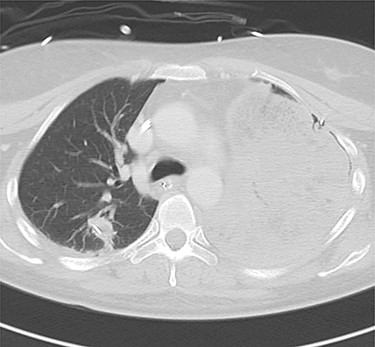

Computed tomography images of 2 days after initial emergency operation.